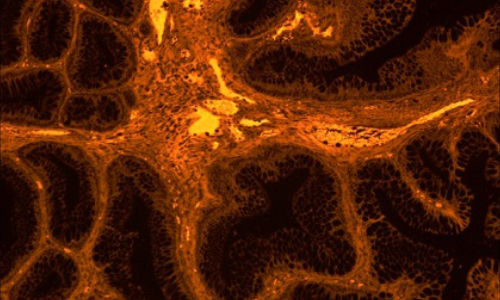

Dhyana 400DC(簡(jiǎn)稱(chēng):400DC)是一款前照式彩色sCMOS 相機(jī)。它兼具科研級(jí)靈敏度和真實(shí)色彩還原能力,具有寬闊的視野和卓越的動(dòng)態(tài)范圍,即使在弱光下也能拍攝高質(zhì)量彩色圖像。

采用高靈敏彩色sCMOS圖像芯片,兼具科研級(jí)的靈敏度和真實(shí)色彩還原能力,無(wú)論明場(chǎng)還是暗場(chǎng)拍攝,都能清晰拍攝細(xì)節(jié)豐富的彩色圖像。